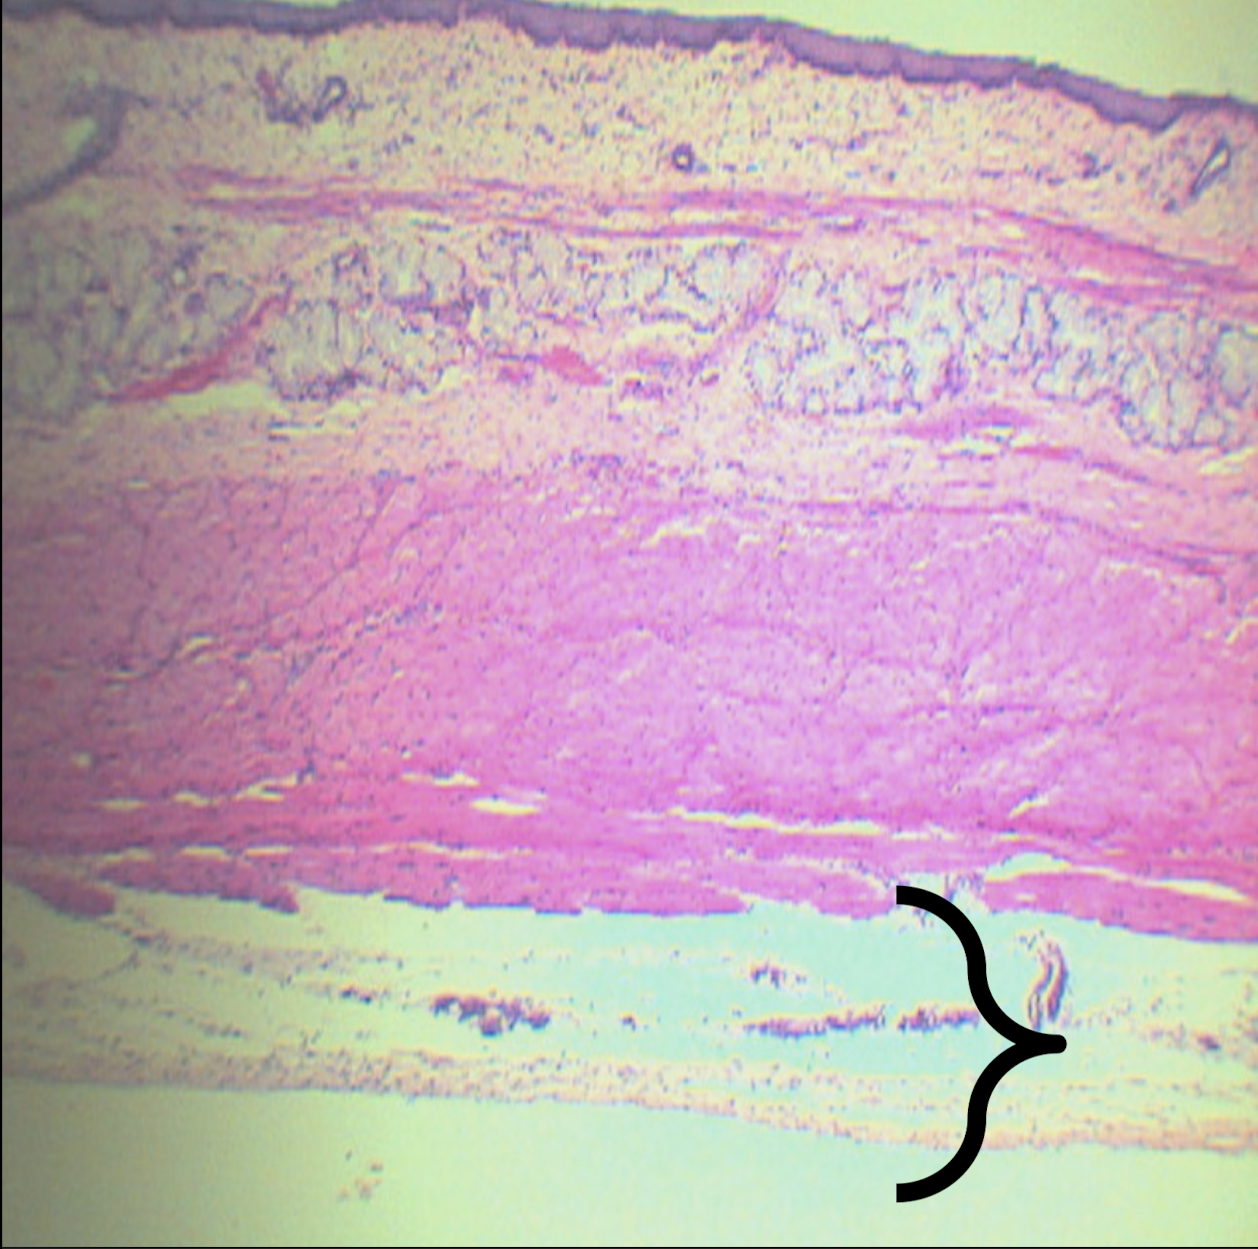

Scanner View of ESOPHAGUS

A: mucosa

B: submucosa

C: tunica muscularis

D: tunica adventitia/serosa

Identify the structure